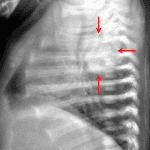

- Right posterior mediastinal mass measuring approximately 2.5 x 2.5 cm on the frontal view with associated rib splaying (right third and fourth ribs) and anterior displacement of the trachea

- No focal airspace opacification, pleural effusion, or pneumothorax

- Normal size and configuration of the cardiothymic silhouette

- Posterior mediastinal mass (thoracic neuroblastoma)

Right posterior mediastinal mass measuring approximately 2.5 x 2.5 cm on the frontal view with associated splaying of the right third and fourth ribs and anterior displacement of the trachea. Recommend chest CT for further evaluation.

No focal airspace opacification, pleural effusion, or pneumothorax.

Normal size and configuration of the cardiothymic silhouette.